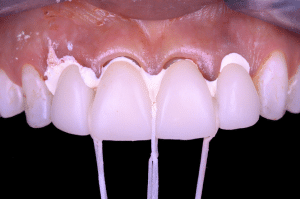

Fig 2.

Avant de procéder au scellement des éléments provisoires, des brins de fils interdentaire sont noués autour de chaque embrasure, par un nœud simple.